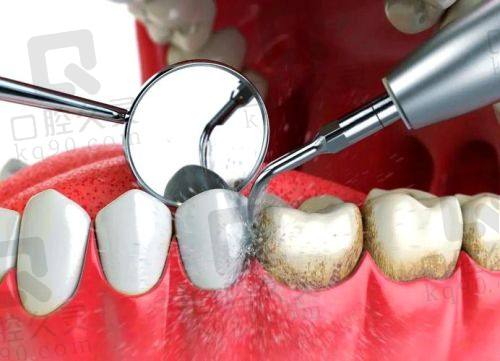

拥有精良的设备和诊疗技术,如cbct机、超声洁治器、根管测量仪、口腔内窥镜、itero口内扫描仪等,能实现系统化、数字化、定制化的口腔诊疗服务。医疗团队来自国内各大口腔学院,临床经验多,技术水平较高。